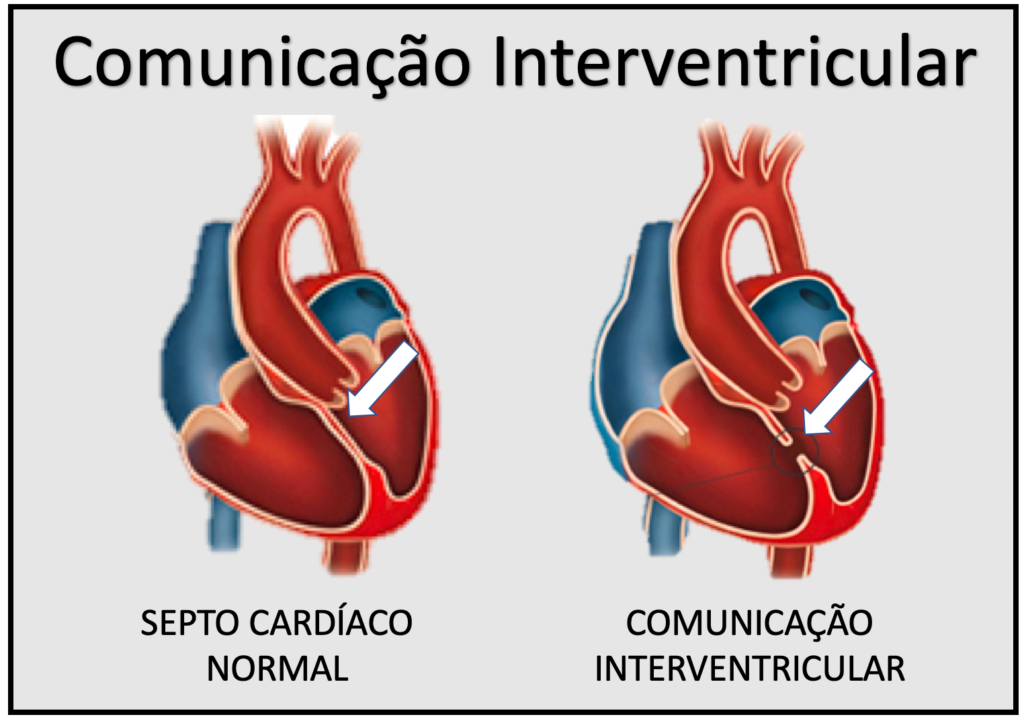

O laudo que solicitou a cirurgia para o bebê foi assinado pelo cirurgião cardiovascular pediátrico Wilson Silveira, em fevereiro. No documento, ele explicou que B. estava em estado crítico e com evolução progressiva do problema, o que o colocava em risco de morte. Ele lembra que a Comunicação Interventricular (CIV) é um dos defeitos cardíacos congênitos mais comuns e pode variar de pequenas aberturas que se fecham sozinhas a grandes defeitos que exigem intervenção cirúrgica.

Quando há uma abertura no septo interventricular (parede que separa os ventrículos), o sangue rico em oxigênio do ventrículo esquerdo passa para o ventrículo direito, misturando-se com o sangue pobre em oxigênio. Isso sobrecarrega os pulmões e o coração, o que pode levar à insuficiência cardíaca.